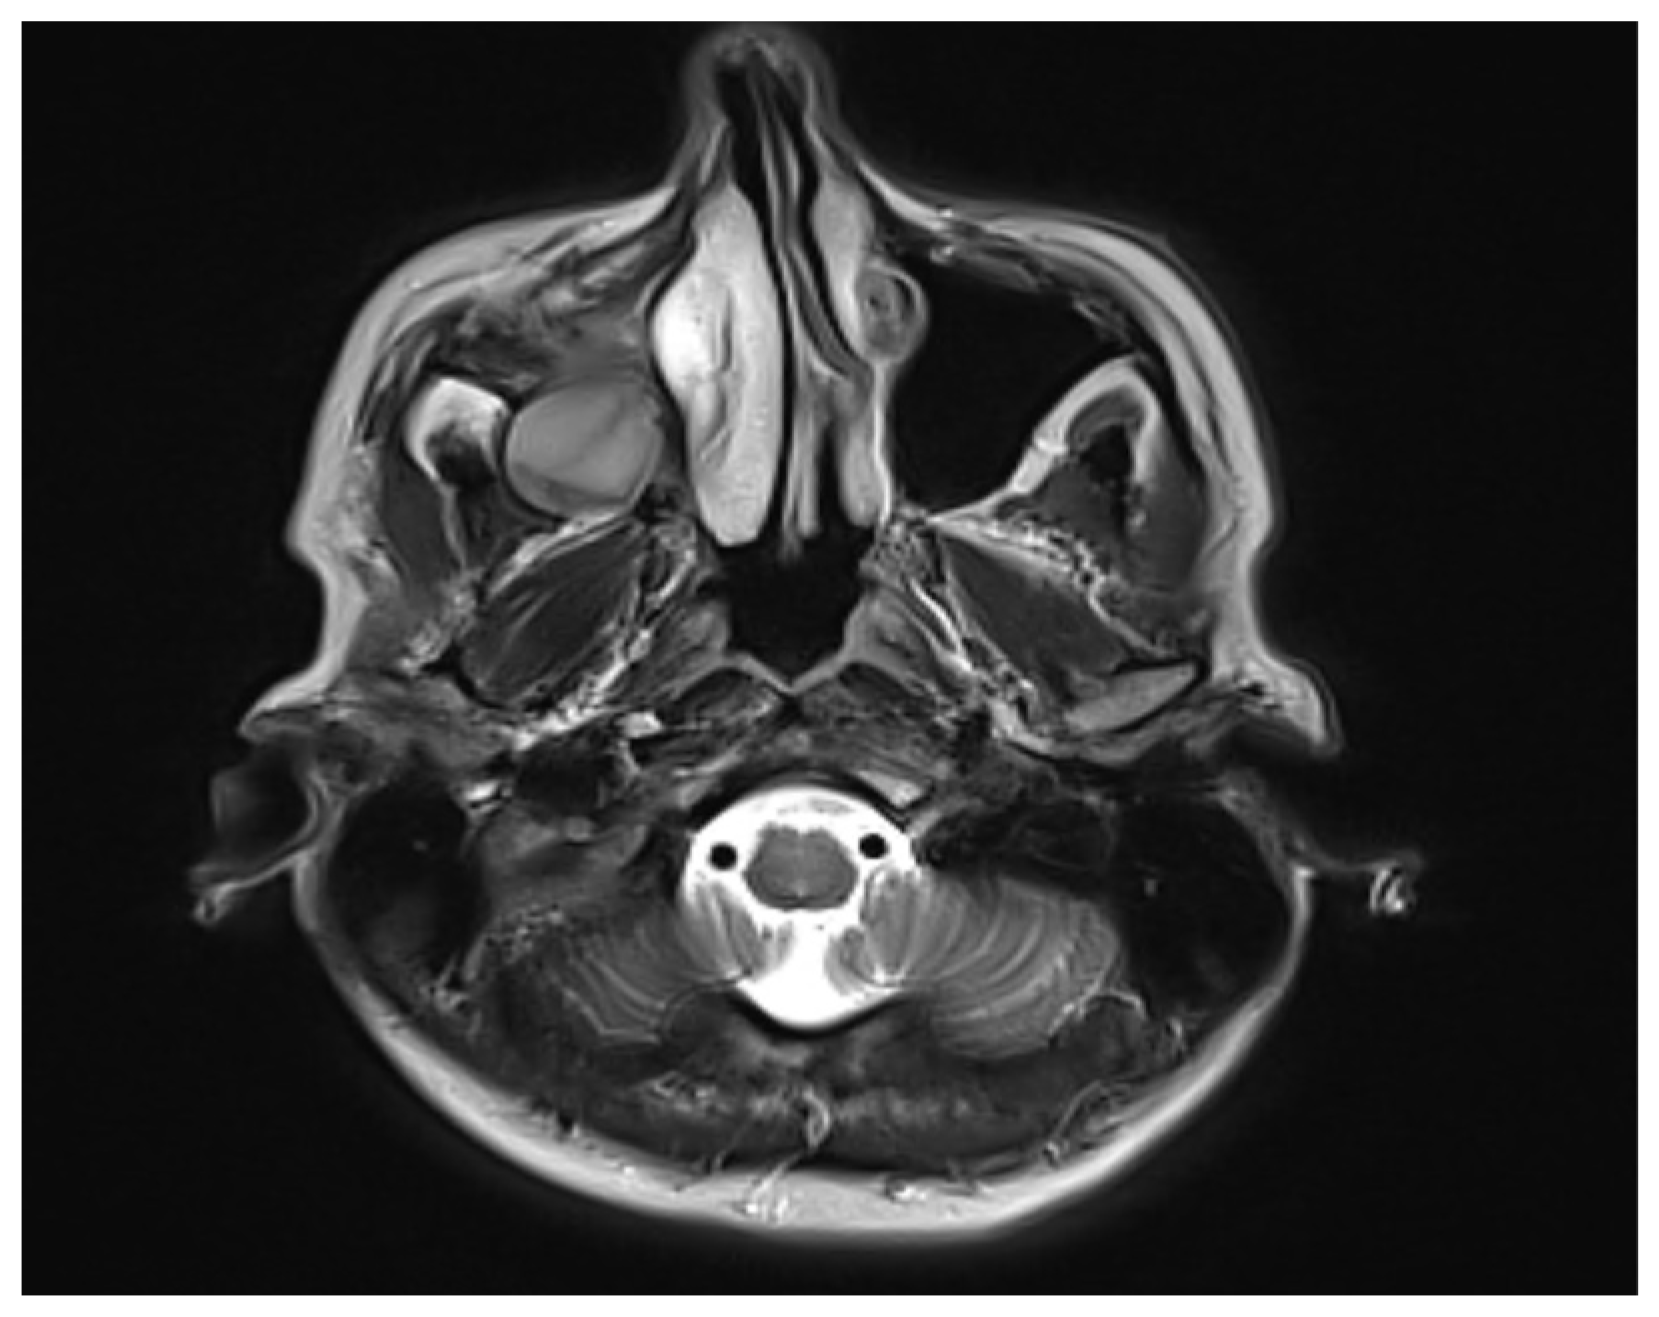

Concurrent Onset of Central Retinal Vein Occlusion and Inflammation of a Large Maxillary Odontogenic Cyst: Case Report and Analysis

2. Case Presentation